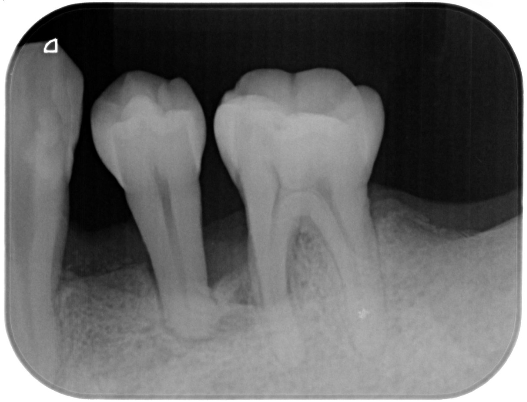

症例2

| 患者様データ | 50代 女性 |

| 来院時の主訴 | 「歯茎から出血する。口の中が全体的に痛い。」 |

| 医院の診断 | 重度の歯周病(壊死性潰瘍性歯周炎) |

| 通院期間 |

2年 |

| 来院回数 | 24回 |

| 治療費 | 総額:220,000円(税抜)+歯周基本治療は保険適用診療 【内訳】 保険適用診療:歯周病検査・歯磨きや生活習慣指導・歯石取りクリーニング 自由診療:歯周組織再生療法220,000円(費用は範囲によって異なります。) |

| リスクと副作用 | 定期的なメインテナンスが必要、正しい歯磨き習慣・生活習慣が必要不可欠 |

| ここがこだわりのポイント!☝ | 少しチャレンジングは症例ではありますが、歯周病によって無くなってしまった歯周組織(歯根膜・セメント質・骨・歯肉)が手術により改善しました。 |